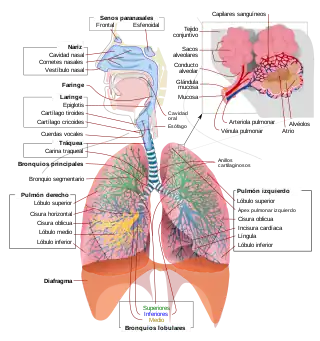

La mayor parte de los animales disponen de sistemas respiratorios que tiene la función de intercambiar gases entre sus células y el ambiente que los rodea, su estructura y función es muy variable dependiendo del tipo de organismo. El aparato respiratorio o sistema respiratorio es el conjunto de órganos que sirven para intercambiar gases con el medio ambiente. En los vertebrados terrestres está formado por las vías aéreas y los pulmones. A través de las vías aéreas, el aire circula en dirección a los pulmones, y en estos órganos la sangre capta el oxígeno y se desprende del dióxido de carbono.[1][2]

El órgano principal del aparato respiratorio humano y de los animales mamíferos es el pulmón. En los alveolos pulmonares se produce mediante difusión pasiva el proceso de intercambio gaseoso, gracias al cual la sangre capta el oxígeno atmosférico y elimina el dióxido de carbono (CO2) producto de desecho del metabolismo.[3] El aparato respiratorio humano está constituido por las fosas nasales, boca, faringe, laringe, tráquea y pulmones. Los pulmones constan de bronquios, bronquiolos y alveolos pulmonares.[4]

El aparato respiratorio humano consta de los siguientes elementos:

- Fosas nasales: Son dos amplias cavidades cuya función es permitir la entrada y salida del aire, el cual se humedece, filtra y calienta a través de unas estructuras llamadas cornetes.

- Faringe: Estructura con forma de tubo situada en el cuello y revestido de membrana mucosa; conecta la cavidad bucal y las fosas nasales con el esófago y la laringe.

- Laringe: Es un conducto que permite el paso del aire desde la faringe hacia la tráquea y los pulmones. En la laringe se encuentran las cuerdas vocales que dejan entre sí un espacio llamado glotis.

- Cuerdas vocales. Son dos repliegues situados en la laringe que vibran cuando el aire los atraviesa produciendo la voz.

- Glotis. Es la porción más estrecha de la luz laríngea, espacio que está limitado por las cuerdas vocales.

- Epiglotis: La epiglotis es un cartílago situado encima de la glotis que obstruye el paso del bolo alimenticio en el momento de la deglución evitando que este se vaya al sistema respiratorio. Marca el límite entre la orofaringe y la laringofaringe.

- Tráquea: Es un conducto en forma de tubo que tiene la función de hacer posible el paso del aire entre la laringe y los bronquios. Su pared está reforzada por un conjunto de cartílagos con forma de C que dificultan que la vía se colapse por compresión externa sobre el cuello.[6]

- Pulmones: Órganos cuya función es realizar el intercambio gaseoso con la sangre. Dentro de cada pulmón, el árbol bronquial se divide progresivamente dando ramificaciones cada vez más pequeñas. La tráquea da origen a los dos bronquios principales que se dividen en bronquios secundarios o lobulares. Cada bronquio lobular se divide en bronquios terciarios o segmentarios que se dividen en bronquiolos. El bronquiolo continúa el proceso de ramificación y da origen al bronquiolo terminal de donde parten los bronquiolos respiratorio que es donde se encuentran los sacos alveolares.

- Bronquio: Conducto tubular fibrocartilaginoso que conduce el aire desde la tráquea hasta los bronquiolos.

- Bronquiolo: Conducto que conduce el aire desde los bronquios hasta los alvéolos.

- Alvéolo: Los alveolos están situados al final de las últimas ramificaciones de los bronquiolos. Tienen la forma de pequeños sacos y son el lugar en el que se produce el intercambio de gases con la sangre. Su pared es muy delgada, pues está constituida por una capa unicelular, es decir formada por una única célula. Sumando los dos pulmones, el organismo humano dispone de alrededor de 600 millones de alveolos que si se desplegaran en su totalidad ocuparían una superficie de 60 m², esta enorme superficie es la que hace posible obtener la cantidad de oxígeno necesaria para las funciones vitales.[6]

- Músculos intercostales: Músculos situados en el espacio existente entre dos costillas consecutivas. Tienen un importante papel para movilizar el tórax durante la inspiración.

- Diafragma: Músculo que separa la cavidad torácica de la cavidad abdominal. Cuando se contrae baja y aumenta el tamaño de la cavidad torácica provocando la inspiración. Cuando se relaja sube, disminuye el tamaño de la cavidad torácica y provoca la espiración.

- Pleura y cavidad pleural: La pleura es una membrana serosa que recubre ambos pulmones. Consta de dos capas, la pleura parietal en contacto con la pared del tórax y la pleura visceral en contacto con los pulmones. Entre ambas capas queda un espacio que se llama cavidad pleural. La presión en la cavidad pleural es menor que la presión atmosférica lo cual hace posible la expansión de los pulmones durante la inspiración.